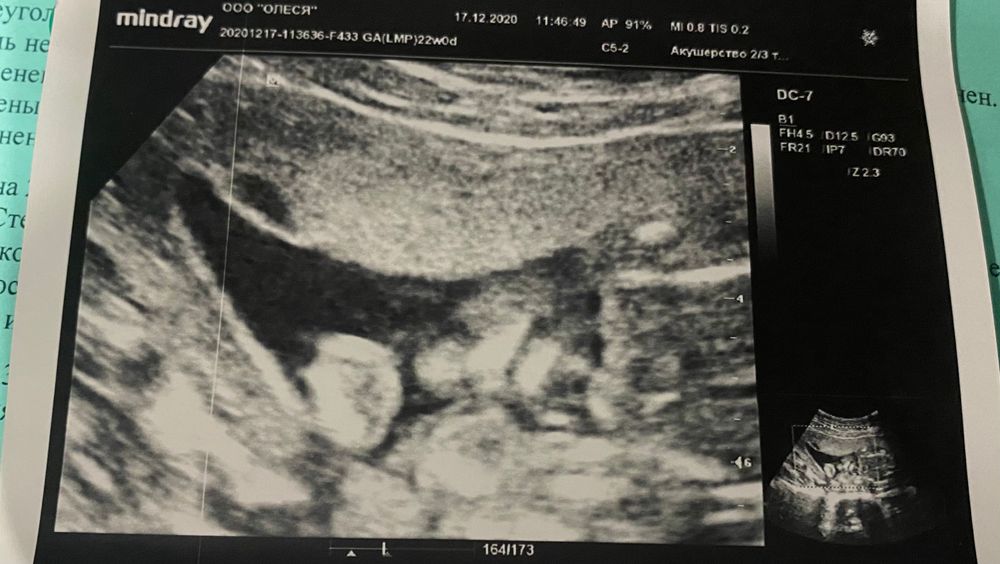

Алина Демина в Здоровье будущей мамы 5 лет Что показано на узи? Вопросы про УЗИ, обследования и анализы: что, где, как, когда? Не понимаю что отображено на узи в 19 недель. Помогите, пожалуйста) Посмотрите еще 20 записей на эту тему Отменить Ответить ssvetick oopss для меня абра-кадабра какая-та 🙈 19.12.2020 Ответить YanaM Я вижу губы, носик 17.12.2020 Ответить Коагулограмма повышены значения Узи 11 недель Чаты Беременных Выберите чат: Январята-2026 Февралята-2026 Мартята-2026 Апрелята-2026 Майчата-2026 Июнята-2026 Июлята-2026 Августята-2026